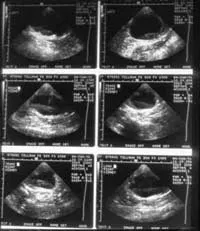

Abdominal radiographs will show only an enlarged kidney or kidneys (Figure 2A), but excretory urography will show renal pelvis dilatation (Figure 2B). Ultrasonography will also show hydronephrosis, renal parenchymal disarray, and necrotic debris in the renal collecting system (Figure 3).

Abdominal ultrasonography (from patient in Figure 2) showing hydronephrosis and necrotic debris in both renal pelvises (A); close-up view of the right kidney (B).